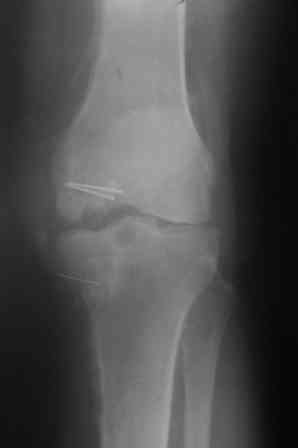

Автотравма 26.06.05. Операция 16.07.05: Открытая репозиция мыщелков правого бедра и б/б кости, остеосинтез пластинами и винтами.

2.02.06 - Плановая операция для удаления металлоконструкций. После операции нагноение в обасти раны. Рана зажила, но образовалось несколько свищей. 25.06.06 - контрольные снимки: диагноз - хронический посттравматический остеомиелит в стадии обострения. На руках имею многочисленные рентген - снимки, обследования( КТ, МРТ, сцинтиграфия). ПРошу всех кто может помочь с информацией куда следует обратиться ( кроме ЦИТО) и проперироваться) . С ув. Александр 28 лет (молодой папаша).